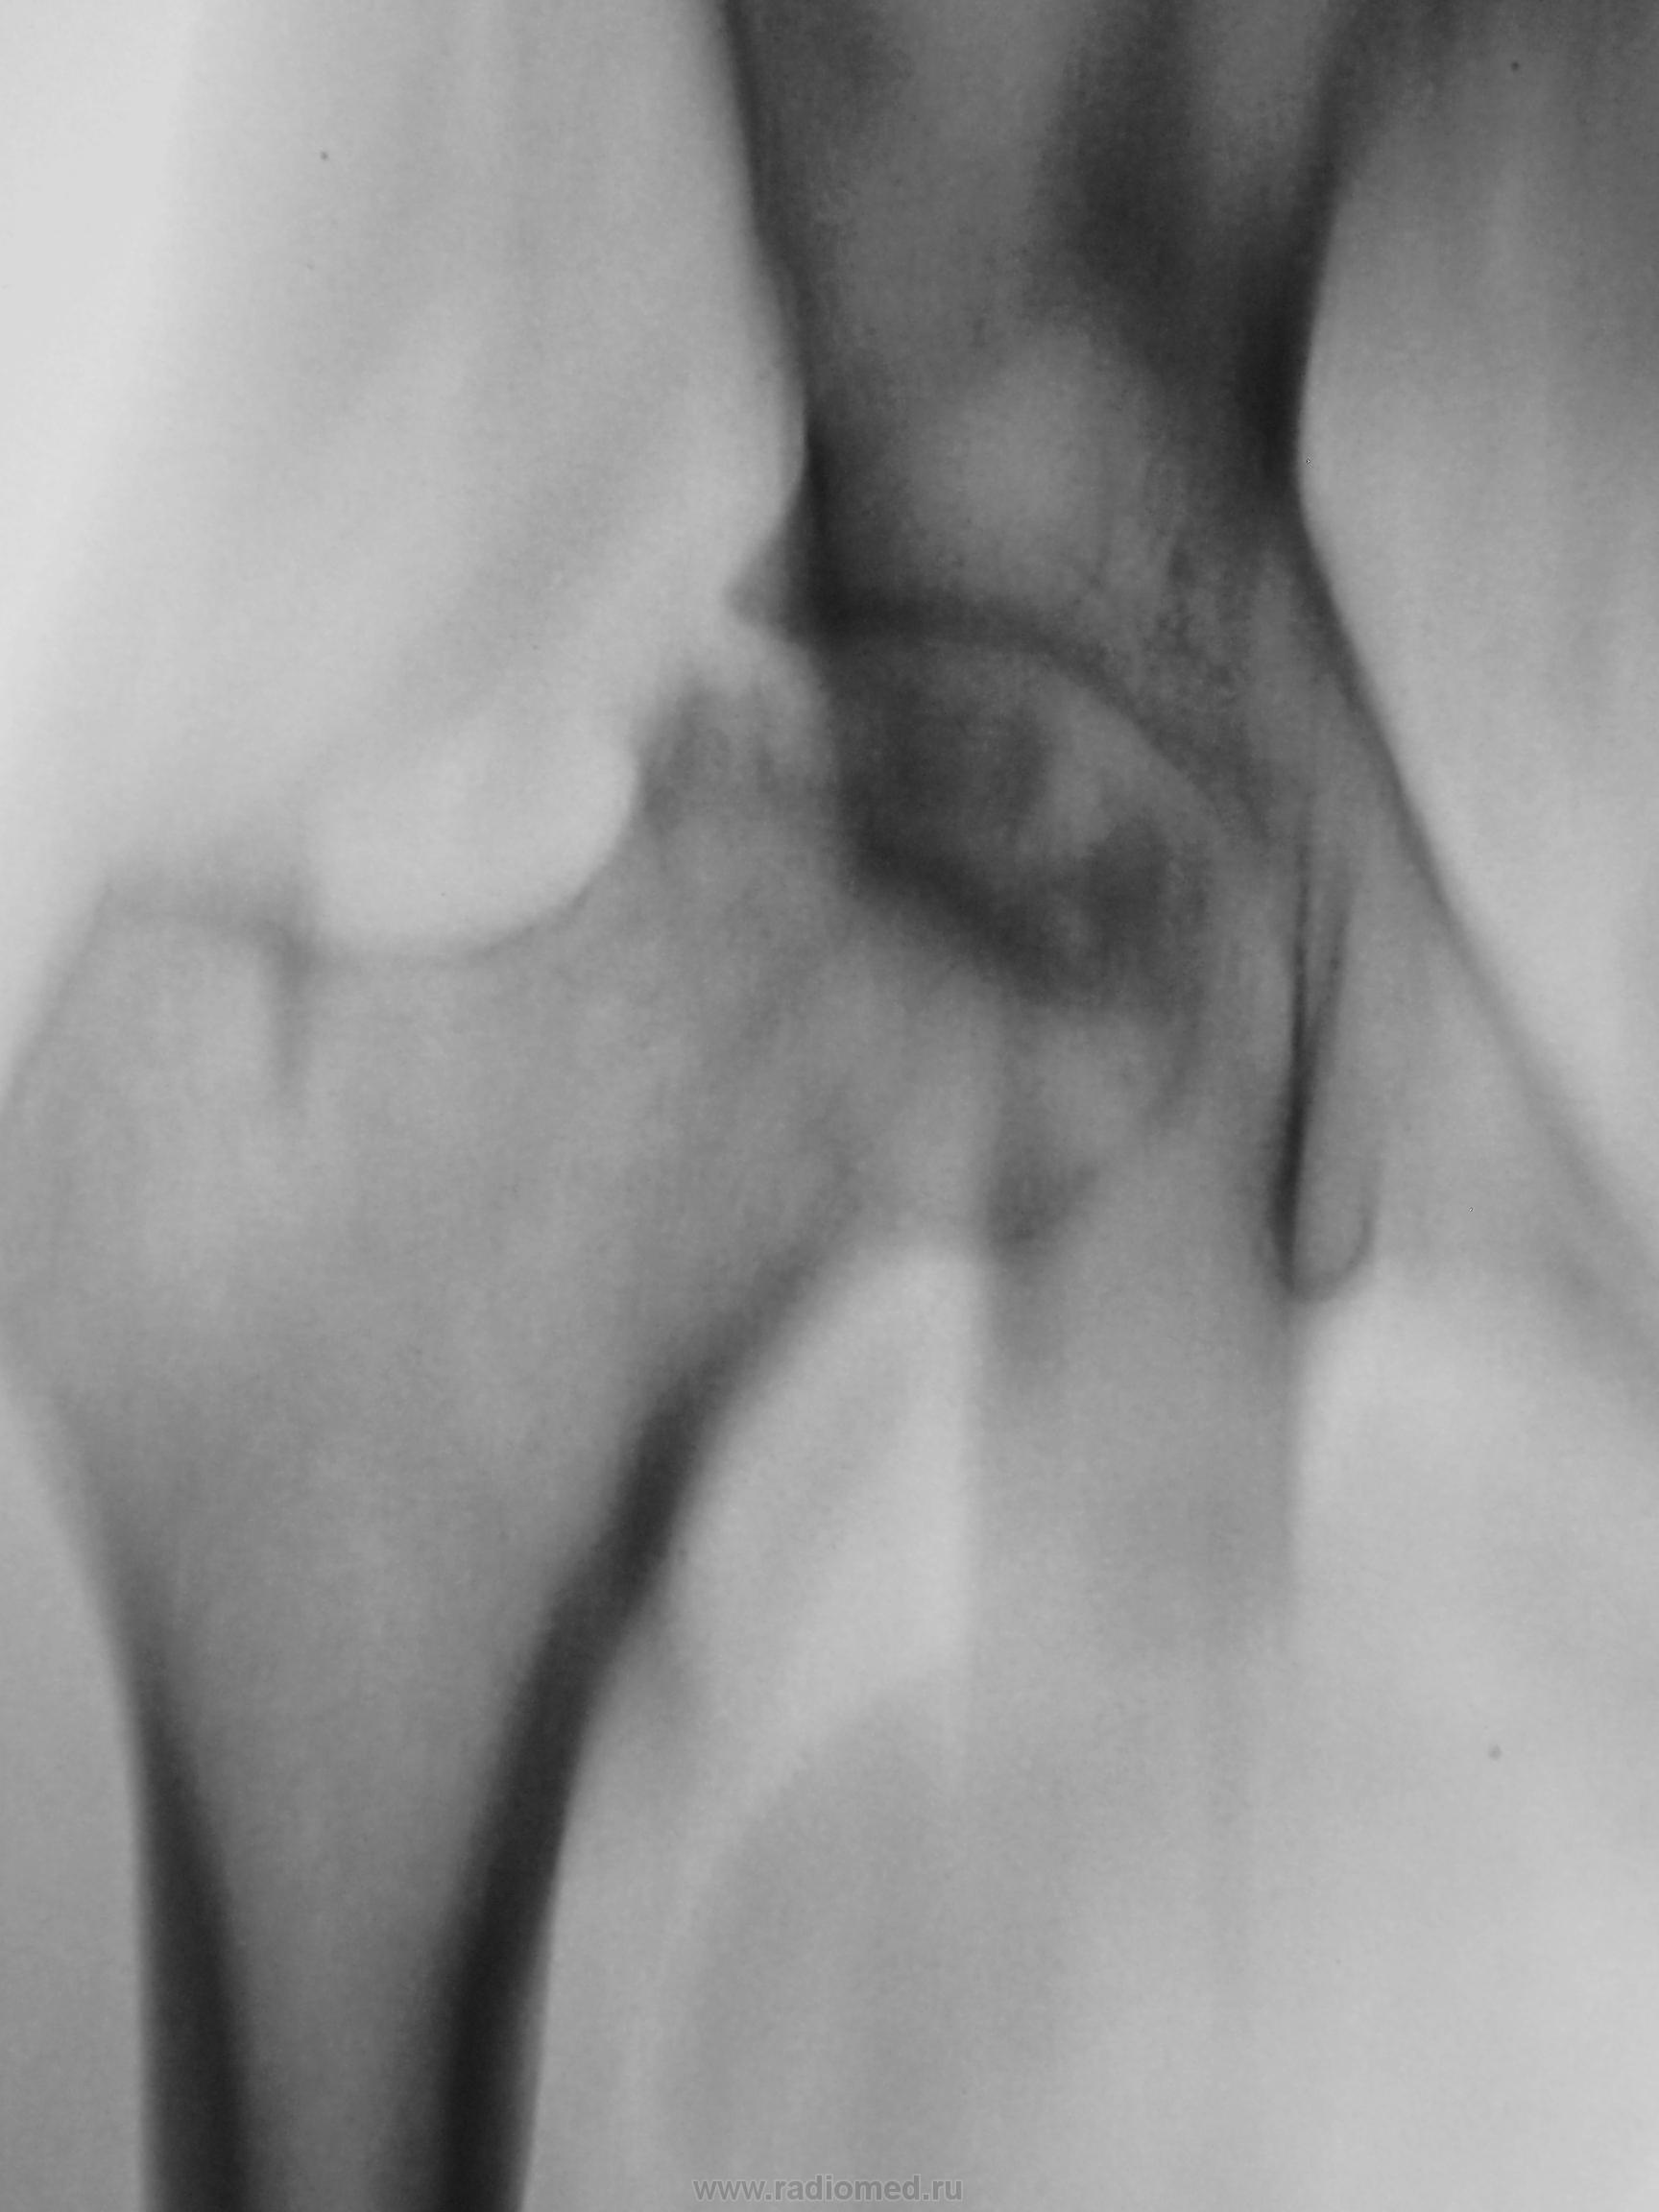

Тазобедренный через год.

В своё время подмеченное Вами, не было достойно оценено, хотя "мнения были", и через год мы "поимели" следующее....

Снимки добавлены.

Ну вот, он и есть асептический некроз головки бедра.

Год назад была 1 стадия, сейчас импрессия,фрагментация. Протез нужен, дальше будет только хуже,т.к. вовлечение вертлужной впадины неизбежно.

Первые снимки - вторая стадия, последние снимки - пятая. О протезировании задуматься уже даже поздно. Еще 0.5-1 год, и будет трудоемко ставить протез.... Похоже, дама вполне терпеливая.

P.S. Евгений опередил... я по 5-стадийной классификации (Рейнберга)))